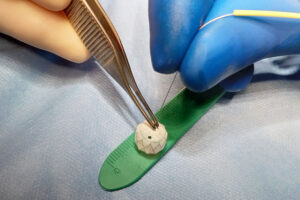

Finding a way to help newborns who can’t immediately have heart treatment

Newborns with complex congenital heart defects (CHD) and pulmonary overcirculation often need treatment as soon as possible. Unfortunately, some of these children are not in good enough health to withstand surgery. To address this challenge, Boston Children’s heart specialists leaned into technological innovation, their experience, and a perseverance that would ultimately confirm their belief that even the ... Read More about Finding a way to help newborns who can’t immediately have heart treatment